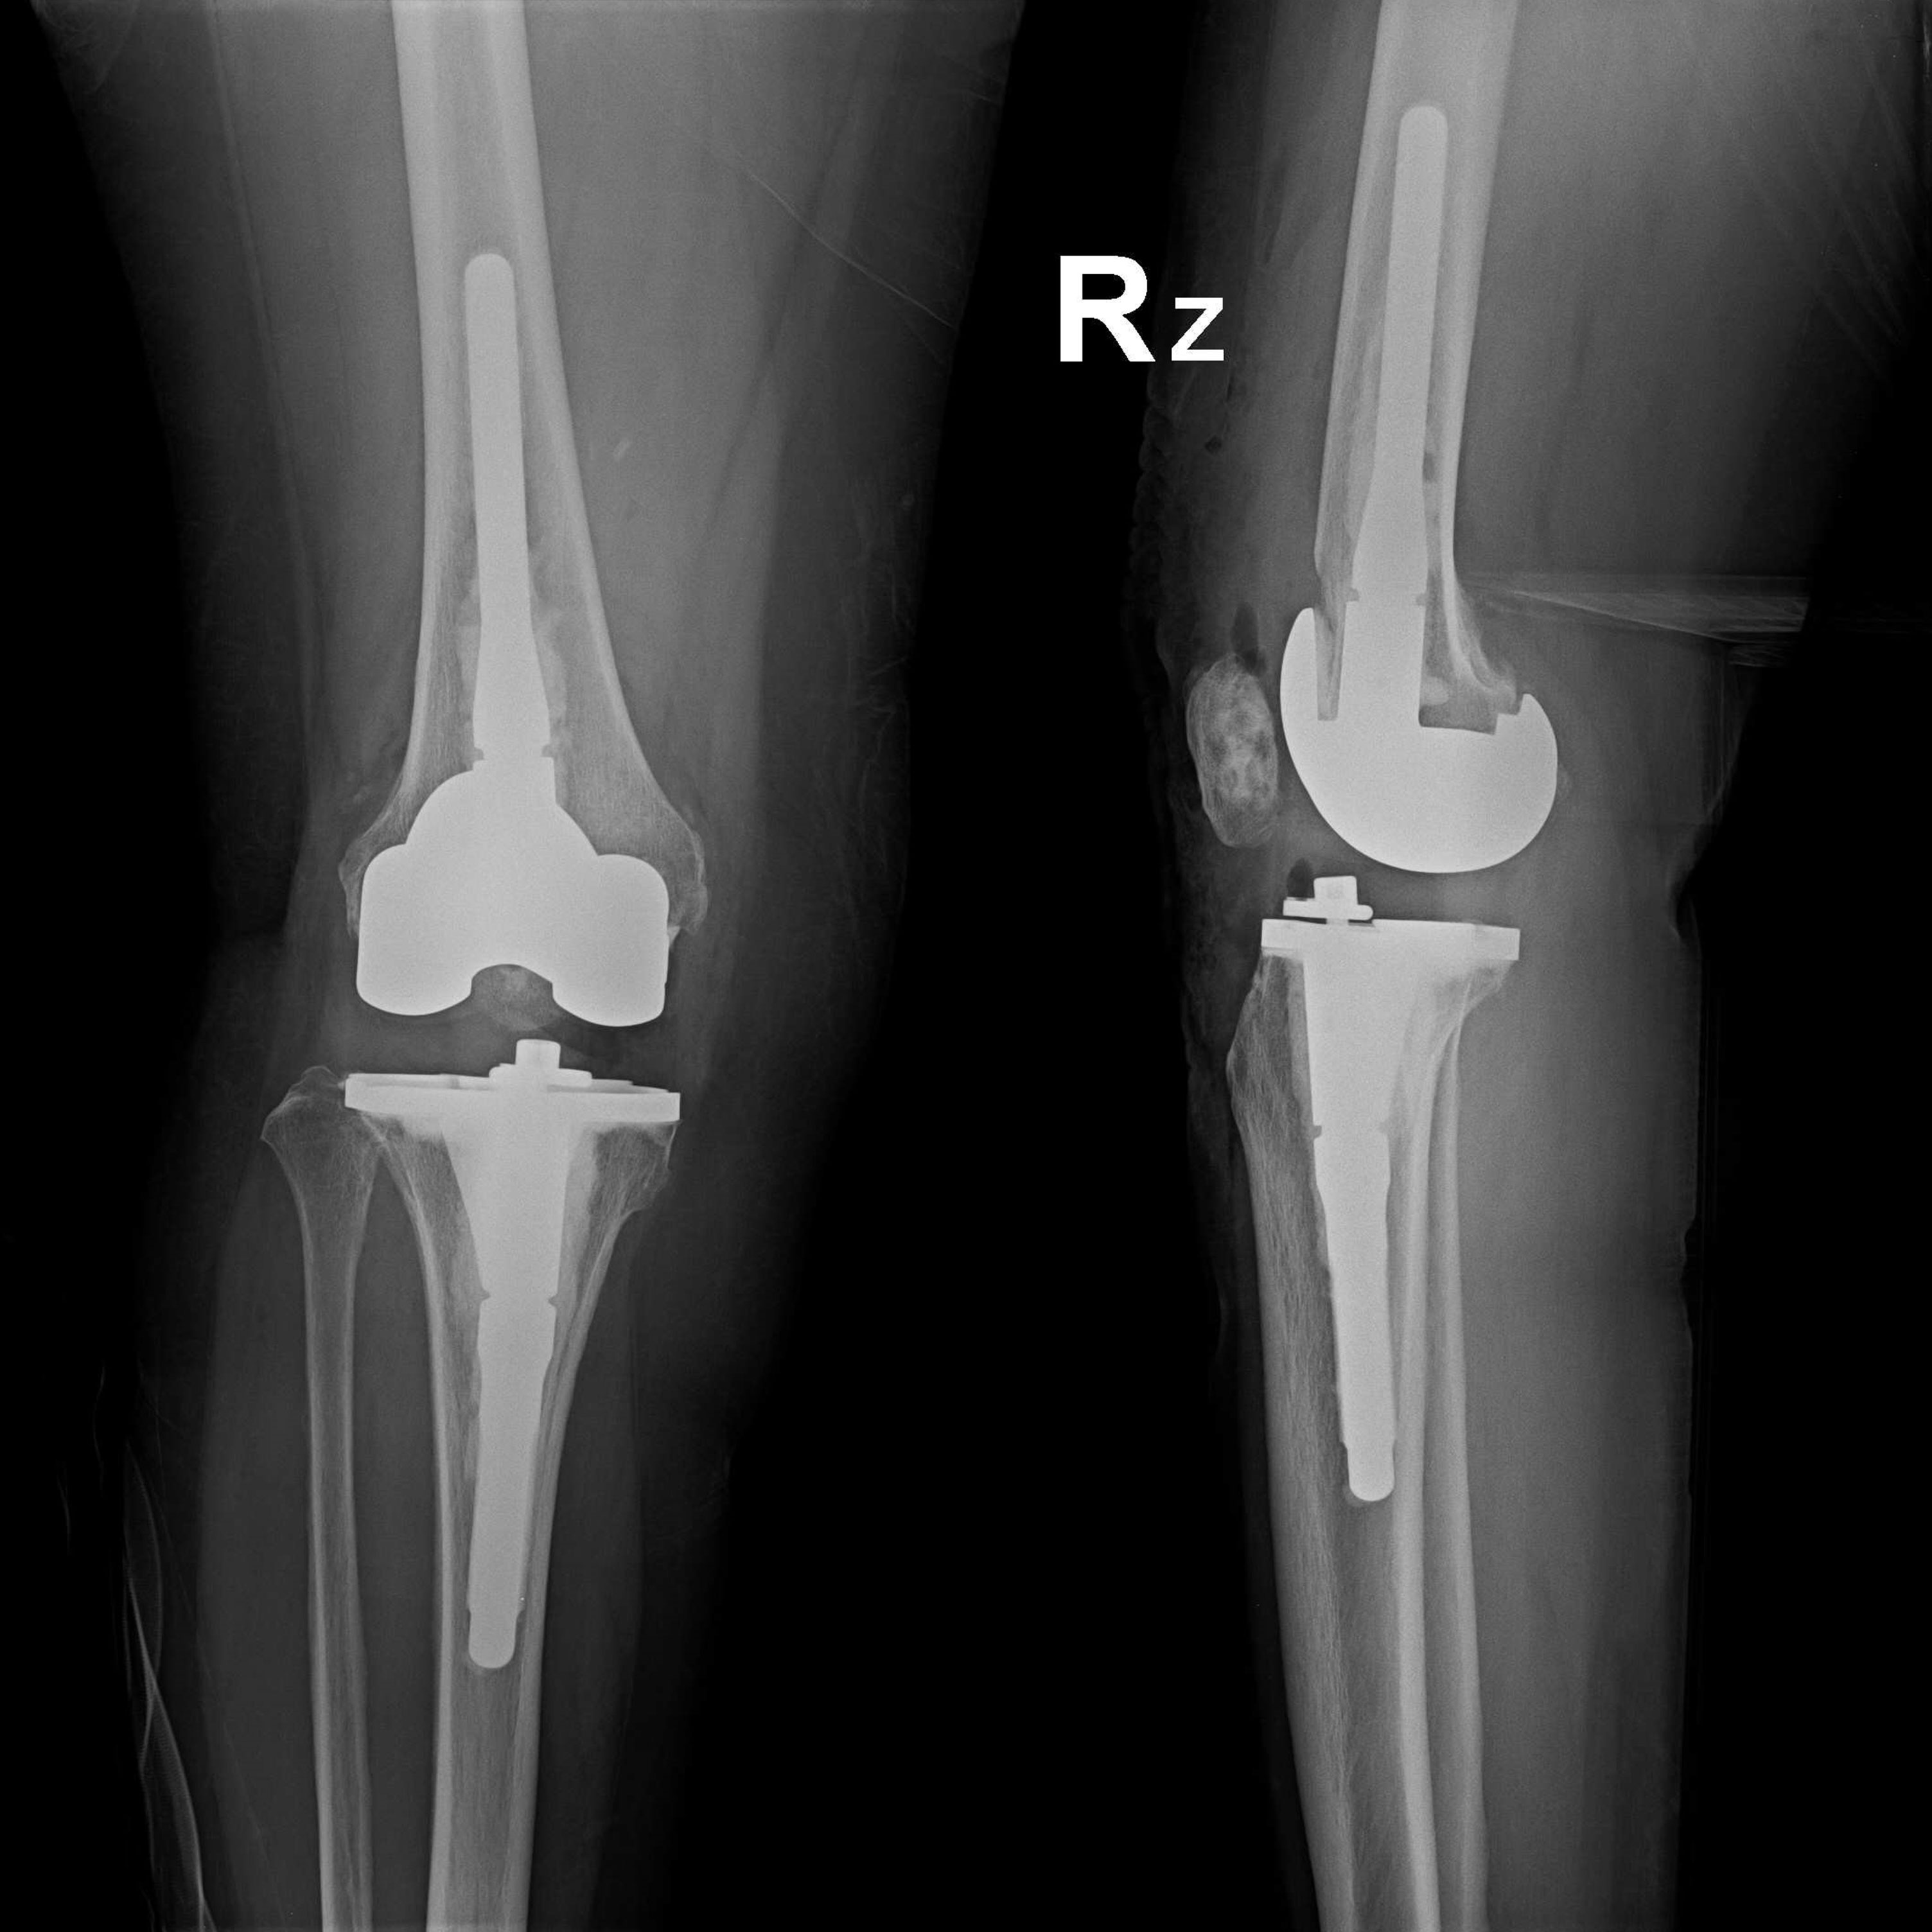

外院失敗本院再置換 首頁 案例分享 膝關節手術 外院失敗本院再置換 蕭女士 69歲 術前 術後 81歲 林女士 術前 術後 蕭女士 69歲 術前 術後 鄒女士 69歲 術前 術後 李女士 74歲 術前 術後 吳女士 71歲 術前 術後 謝女士 65歲 術前 術後